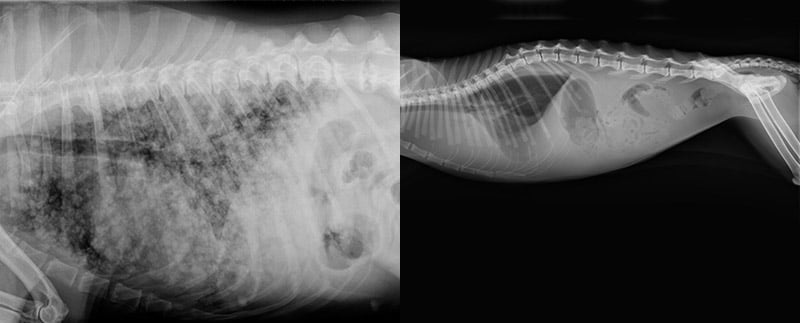

Mit unserem Gerät wird digital geröntgt, das heißt, die Abschwächung der Röntgenstrahlen wird von einem Computer berechnet und bearbeitet, so dass das Bild sofort sichtbar ist und nicht auf einer Folie entwickelt werden muss. Zusätzlich kann das Bild noch bearbeitet werden, um Strukturen ggf. noch deutlicher sichtbar zu machen.

Mit Röntgenstrahlen können vor allem Knochenstrukturen sehr gut dargestellt werden, aber auch Weichteilstrukturen sind oft gut erkennbar. Materialen unterschiedlicher Dichte absorbieren Röntgenstrahlen unterschiedlich stark, so dass die abgeschwächten Strahlen die unterschiedlichen Strukturen aufzeigen. Zum Beispiel absorbieren Knochen die Strahlen fast vollständig, während Weichteilgewebe wie, zum Beispiel die Milz, einen großen Teil der Strahlen durchlassen und somit im Röntgenbild dunkler erscheinen.

Die Lunge und das Herz sowie auch die Gefäße lassen im Röntgen oft Rückschlüsse auf bestehende Erkrankungen zu. Zum Beispiel ist die Vergrößerung der Herzsilhouette ein Hinweis auf eine Herzerkrankung , die mittels Herzultraschall weiter untersucht werden sollte.

Im Lungenröntgen können zum Beispiel Primärtumore oder Metastasen diagnostiziert werden. Aber auch Gewebs- oder Bronchialerkrankungen, wie z.B. Entzündungen, können anhand von Strukturveränderungen gesehen werden.

Abdomen (Bauchraum):

Magen (zum Beispiel bei einer Magendrehung), Darm, Leber, Milz, Nieren, Blase lassen sich ebenfalls gut im Röntgen untersuchen.